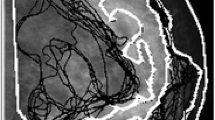

Supplementary Fig. 3 Mediolateral oblique (MLO)-view mammograms from two cases in the dataset. The mammograms from two cases in the dataset are shown. (a) The opinions of all physicians were consistent as “heterogeneously dense.” (b) The opinions of the physicians were divided between “scattered” and “heterogeneously dense